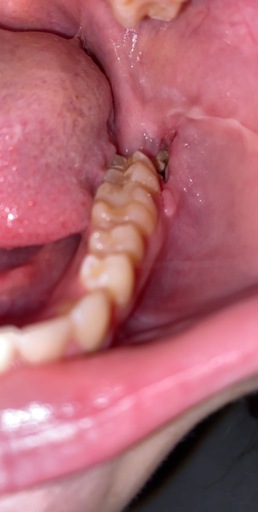

Hi, I have a frenulum on the right side of my mouth. It connects to my gums about 1cm behind the upper and lower back molars. It has become tight and painful. Have you ever seen anything like this? Is it safe to have it cut? I will attempt to add a photo. Thank you, H. Jay Graber

A frenum or frenulum is a small fold of tissue that restricts and secures the motion of a mobile organ. I have not heard of a frenulum in the back of the mouth. It would be best to bring this to the attention of your dentist, especially because it is causing discomfort. I did not see a picture attached to your question, however I am wondering if it is part of your cheek or possibly an impacted tooth that may be causing this discomfort. Use warm salt water rinses several times a day to soothe the tissues until you have a proper exam and diagnosis.

A frenulum or frenum is a small fold of tissue that restricts or secures the motion of a mobile organ. I have not seen a fold of tissue (unless sutured) that connects distal to the molars. There is a frenum that connects your tongue to the floor of your mouth as well as one that attaches your lips to your jaws. Since you are experiencing pain, it is important for you to see your dentist immediately to be sure you do not have an infection or a tooth that is creating swelling in the area.